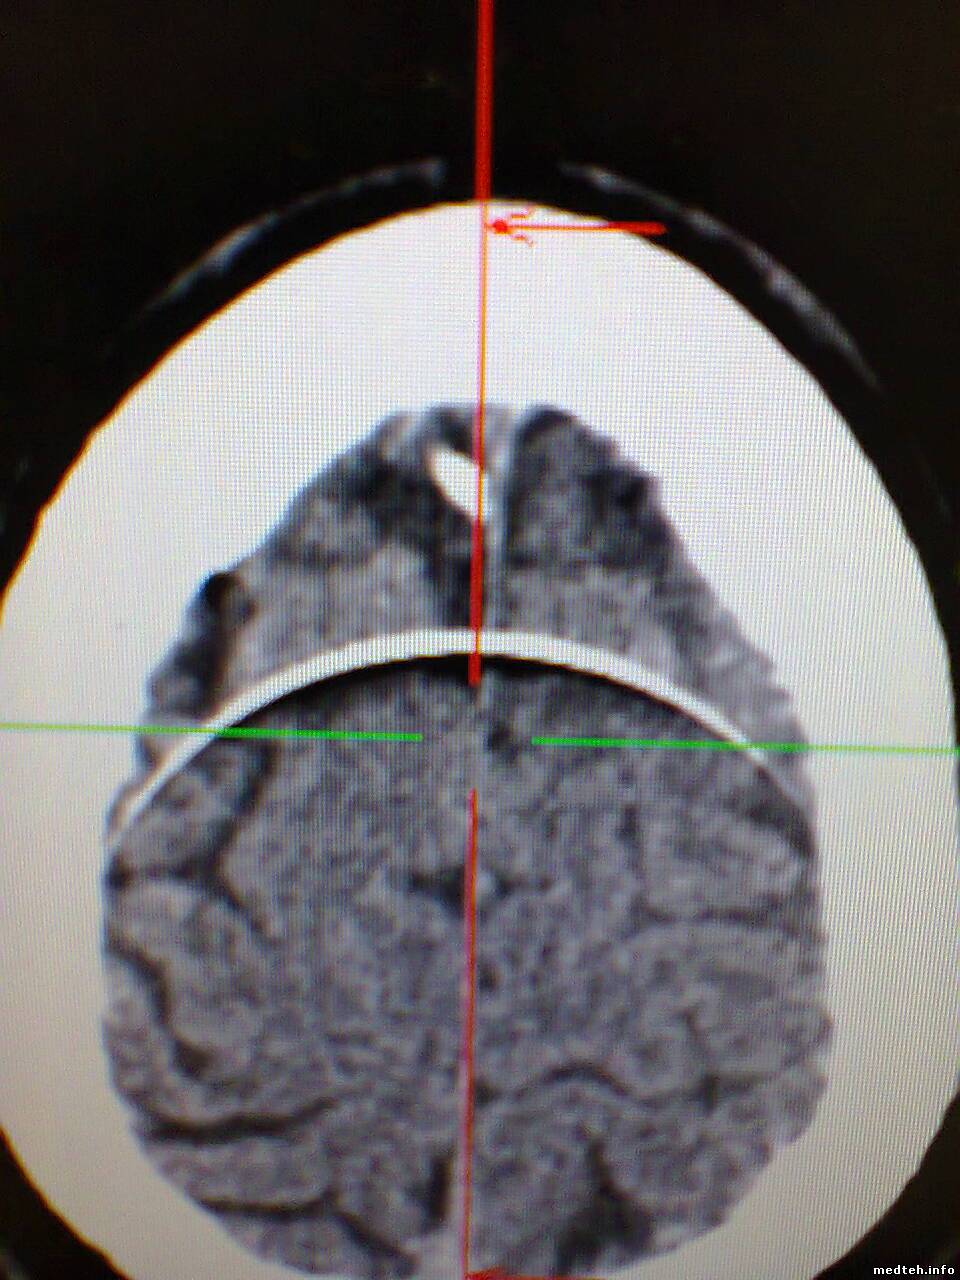

Здравствуйте, появился спиральный артефакт на изображениях, который исчезает примерно на день если провести калибровку по воздуху, думал что дело в модуле датчиков но тест defective channels не показывает ошибок. Что-нибудь кроме датчиков может давать такое изображение? Есть вероятность что детектор как-бы отпаивается? Можно ли тогда запаять его обратно?

1233008.jpg (169.7 Kb) · 7047881.jpg (198.7 Kb) · 0284259.jpg (186.5 Kb) · 0243983.jpg (196.8 Kb) · 3573226.jpg (195.6 Kb)